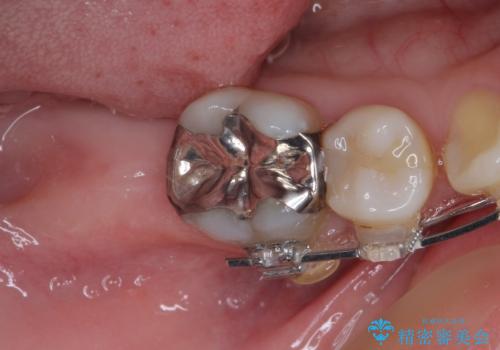

- 口元の突出感と奥歯の欠損を気にして来院された患者様です。

口元の突出感改善には、上下左右の第一小臼歯4本を抜歯し、奥歯の欠損部には矯正治療の途中でインプランを埋入していくこととしました。

矯正治療の後半にインプラント埋入を行うことで、トータルの治療期間を短縮することができました。